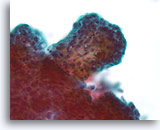

Lobulair carcinoom, Borst FNA, celblok.

Lobulaire carcinoomcellen lijken in het stromaweefsel te zijn ingebed, zodat de indruk wordt gewekt van hypercellulariteit. Dit kan de reden zijn waarom cytologische preparaten van een lobulair carcinoom vaak weinig maligne cellen tonen.

20X

Lobulair carcinoom, Borst FNA, celblok.

Lobulaire carcinoomcellen lijken in het stromaweefsel te zijn ingebed, zodat de indruk wordt gewekt van hypercellulariteit. Dit kan de reden zijn waarom cytologische preparaten van een lobulair carcinoom vaak weinig maligne cellen tonen.

20X

Lobulair carcinoom, Borst FNA, celblok.

Een enkele rij minimaal atypische spaarzame cellen die op en in de stromale fragmenten vastzitten, kan worden waargenomen. Let op de kenmerkende targetoïde intracytoplasmische vacuolen van lobulaire neoplasie.

40X

Lobulair carcinoom, Borst FNA, celblok.

Een enkele rij minimaal atypische spaarzame cellen die op en in de stromale fragmenten vastzitten, kan worden waargenomen. Let op de kenmerkende targetoïde intracytoplasmische vacuolen van lobulaire neoplasie.

40X